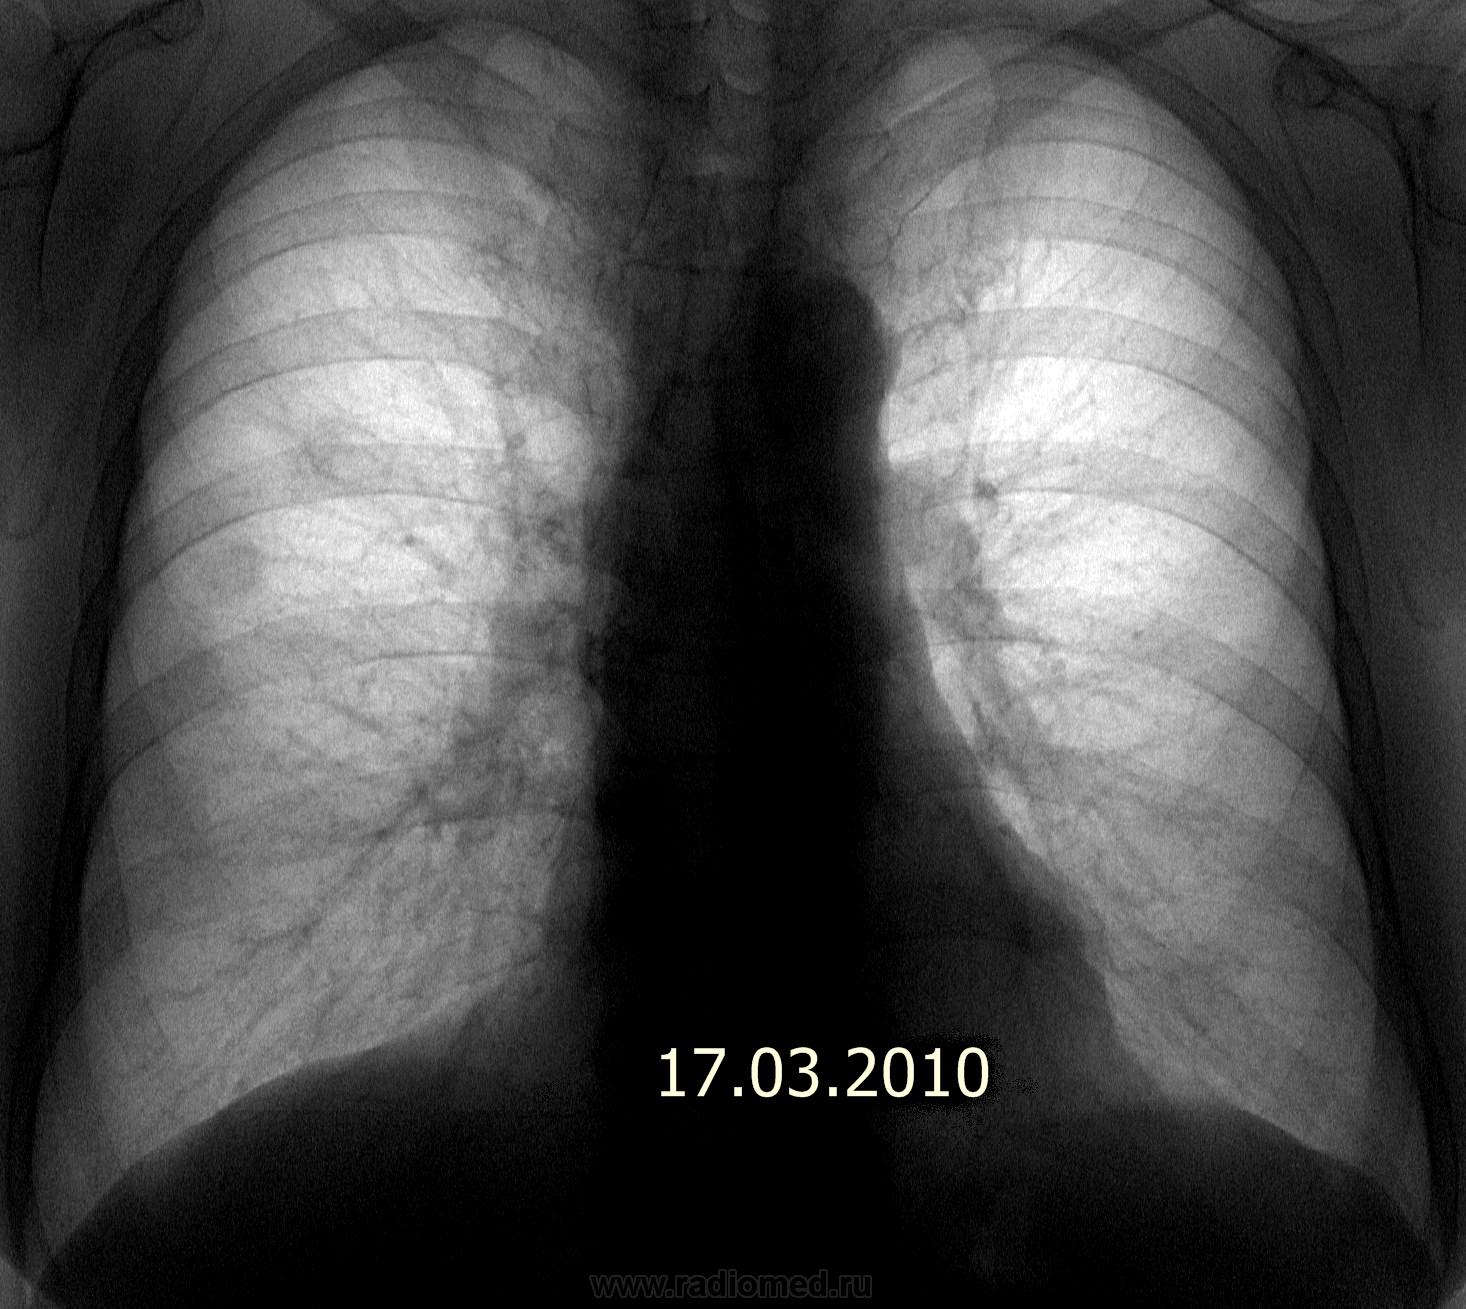

А по снимку от 17.07.09. - показалась гиперплазия правого корня, особенно настораживает тело. В паренхиме - пусто. А вообще, приходится встречаться с такими случаями бурно растущих опухолей, что промежуток в 6 месяцев между флюорографиями пациента не спасает: вот он был (корни не расширены, малоструктурны, паренхима интактна) и вот он пришел (центральный рак, выпирающий по контуру корня с лучистостью и гиповентиляцией верхней доли; на ФБС - карциноматоз трахеи и бронхов, обтурация в\д бронха серой опухолью, цитология - аденокарцинома), а вот через 2 недели его уж и нет на свете (онко:-лечение симптоматическое по месту жительства). Рентгенолог всегда должен быть готов отстоять сою правоту в том, в чем прав.

А по снимку от 17.07.09. - показалась гиперплазия правого корня, особенно настораживает тело. В паренхиме - пусто.

Рентгенология как раз наиболее эффективна для выявления ранних стадий рака легкого (и не только). Проведение КТ-скринга - вопрос чисто экономический, к тому же современные цифровые технологии традиционной рентгенографии вполне приближаются к КТ. Проблема скорее в том, а проводится ли скриниг (по нашему профосмотр) и в каком объеме. В рассматриевом нами случае речь идет не о ранней диагностике, а об обнаружении мтс без выявленного первичного очага.

Поламали копья, и будя - на КТ консолидированные переломы 3,4,5 ребер.